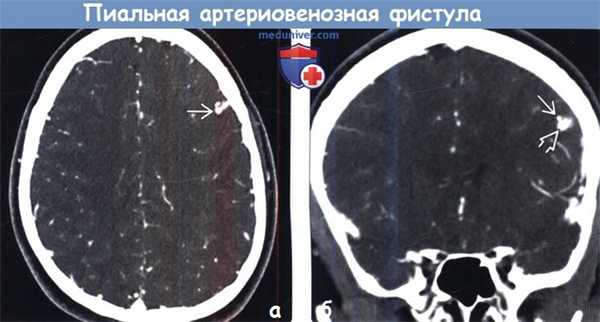

(а) КТ-ангиография, аксиальный срез: у пациента с НГТ определяется расширенный сосуд, лежащий в борозде вдоль поверхности полушария головного мозга.

(б) КТ-ангиография, корональный срез: у того же пациента определяется маленький пучок крошечных артерий, дренируемых в дила тированную вену. Интраоперационно была диагностирована пиальная АВФ.

2. КТ при пиальной артериовенозной фистуле:

• Бесконтрастная КТ:

о Изо-/гиперденсные серпантинные сосуды

• КТ-ангиография:

о Визуализация питающих артерий, дренирующих вен/варикоз-но расширенных вен